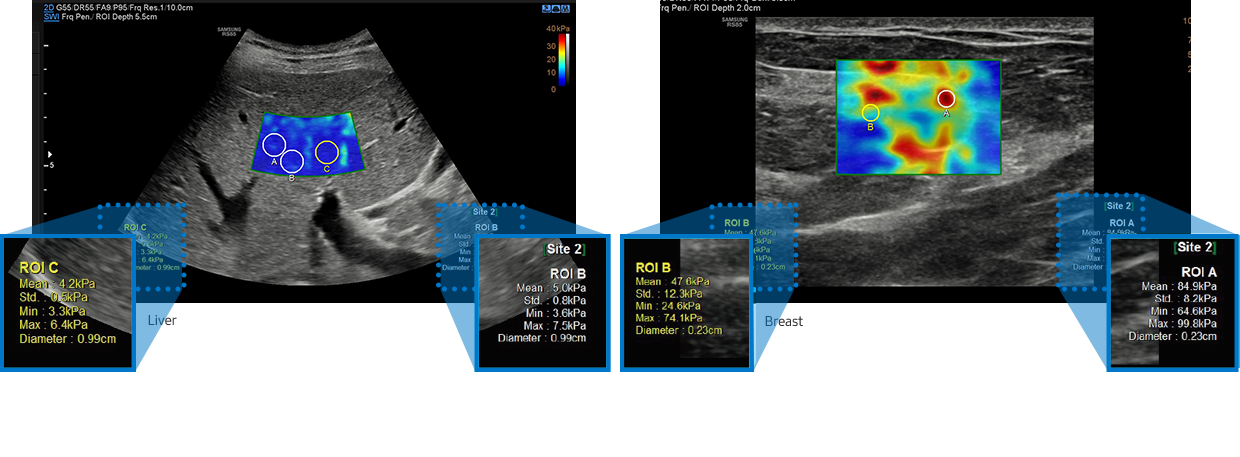

S-Shearwave Imaging™ ¹

Non-invasive quantification method of tissue stiffness

S-Shearwave Imaging™ ¹ allows for non-invasive assessment of the stiffness of tissue/lesions in the breast and liver, by providing an advanced level of diagnostic information. The color-coded elastogram, quantitative measurements (inkPa or m/s), dual or single display option, and user-selectable ROI (position and size) functions are especially useful for the accurate diagnosis of breast and liver diseases.

fatty liver ultrasound (liver stiffness assessment) : S-Shearwave Imaging™, ultrasound for breast (breast stiffness assessment) : S-Shearwave Imaging™